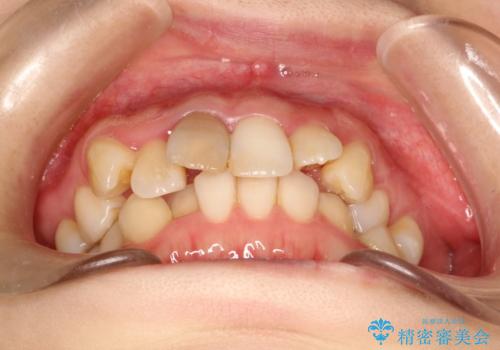

- 上下のがたつきを主訴に来院された患者様です。

上下の前歯と奥歯にがたつきがありました。

上下の奥歯を後方に移動させるのと、歯と歯の間をわずかに削ることでスペースを作り、歯を並べる計画としました。

比較的がたがたの度合いが大きかったですが、しっかりとマウスピースを使用していただけたので、順調に治療を終えることができました。